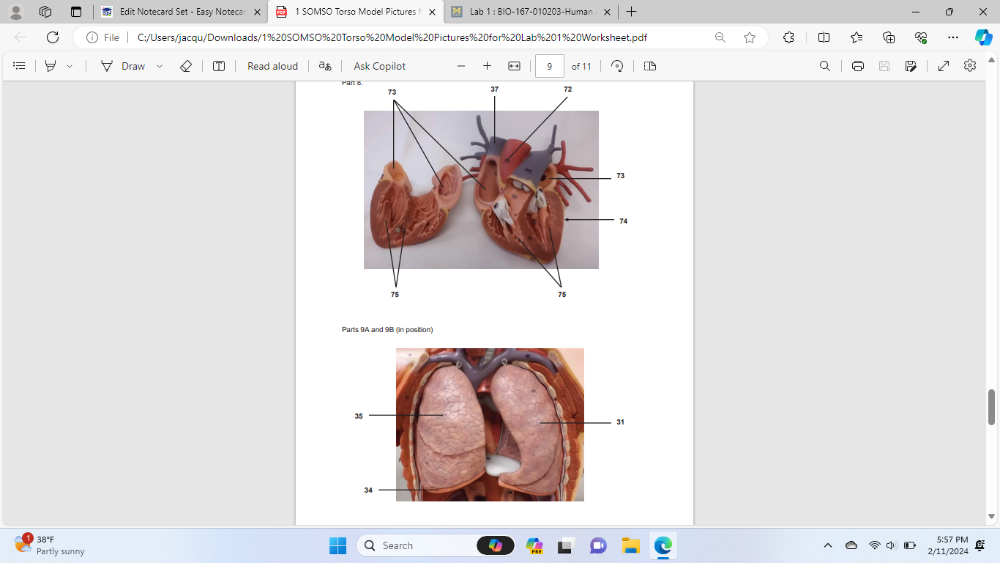

Identify the specific organ labeled 42

inferior vena cava

Identify the specific organ and side labeled 31

left long

Identify the specific muscle labeled 34

Diaphragm

Identify the specific organ and side labeled 35

Right lung

Identify the specific blood vessel labeled 37

superior vena cava

Identify the specific blood vessel labeled 72

ascending aorta

Identify the specific part of the heart labeled 73

left atrium

Identify the specific organ labeled 74

heart

Identify the specific part of the heart labeled 75

ventricle

Identify the specific bone labeled 11

clavicle

identify the specific bone (cut) labeled 6

rib